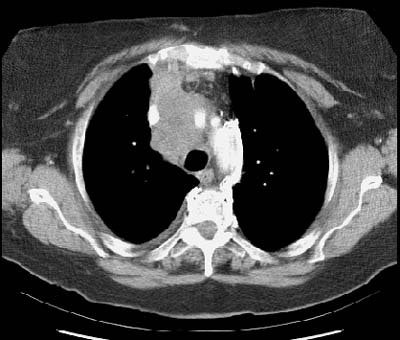

Example of the normal hilar interstitium: The images below are from a patient without bronchogenic carcinoma. The images demonstrate normal hilar lymphatic tissue (yellow arrow right image) which appears as a low density region between the bronchus and pulmonary vessel. A small calcified node is seen on the right (red arrow) in this patient with prior granulomatous disease.   NOTE:  Click image to enlarge.

New Criterion for Determination of Pathologic Hilar Adenopathy

Example 1: This is an example of an N1 node in a patient with a lingular adenocarcinoma (left image). Although not pathologic by short axis size criteria, the lymphatic tissue in the left hilum has a convex border with the adjacent lung (white arrows). This node contained adenocarcinoma at histopathologic analysis. Some authors advocate using the presence of a convex margin of the interstitium with the lung parenchyma to indicate pathologic adenopathy to improve the sensitivity of CT for detecting hilar metastases [36].

Example 2: This patient is an example of a false negative CT for hilar nodal metastases even when applying the suggested new criterion. The patient had a peripheral adenocarcinoma in the left upper lobe (black arrows). The left hilar node (yellow arrows) is not pathologic by size criteria, nor does it exhibit a convex margin with the adjacent lung parenchyma. This is a normal node by CT, however, at histopathologic analysis the node was positive for malignant cells.